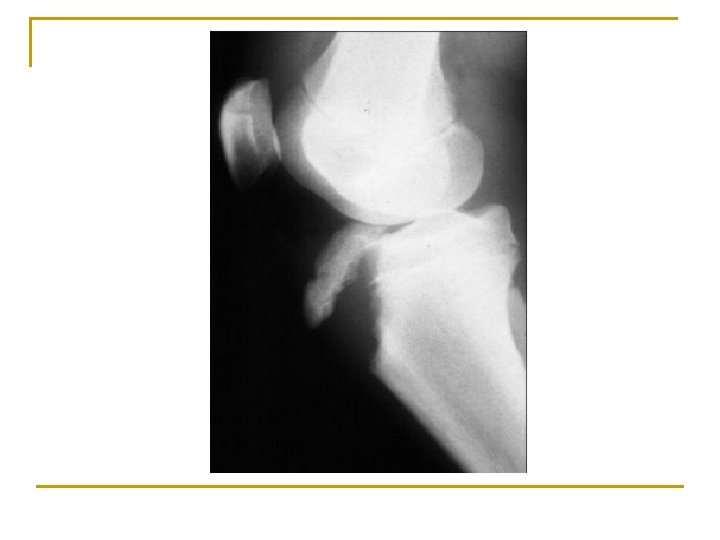

ACL Tears n n n Cause: Direct lateral or valgus blow with the knee flexed and tibia externally rotated, lower leg rotated with the foot planted, or flexion deceleration injury S/S: Hears/feels a ‘pop’ in the knee followed by immediate disability. Laxity of joint. TX: RICE n n n Surgery Rehabilitation ST: Anterior Drawer test, Lachman test